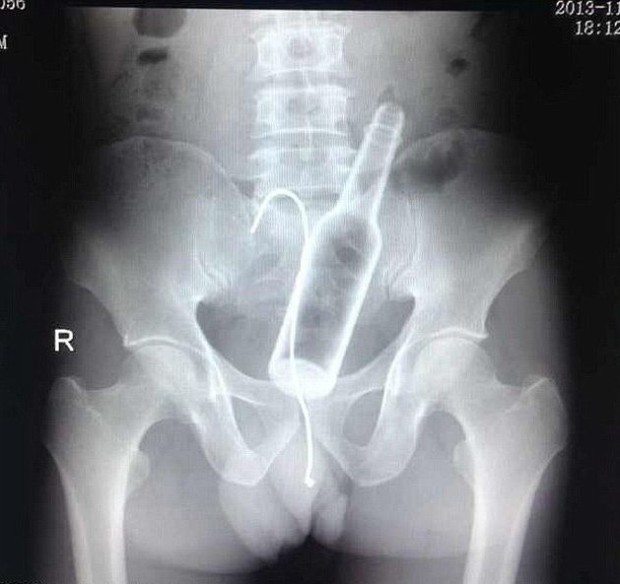

9. A Vibrator And Some Metal Tongs

This man also faced embarrassment when he was forced to seek medical intervention after getting a vibrator lodged inside of himself. Then, not wanting to go to the doctors he tried to fix the problem himself by pulling them out with some cooking tongs. But, he got them stuck inside too.Advertisement